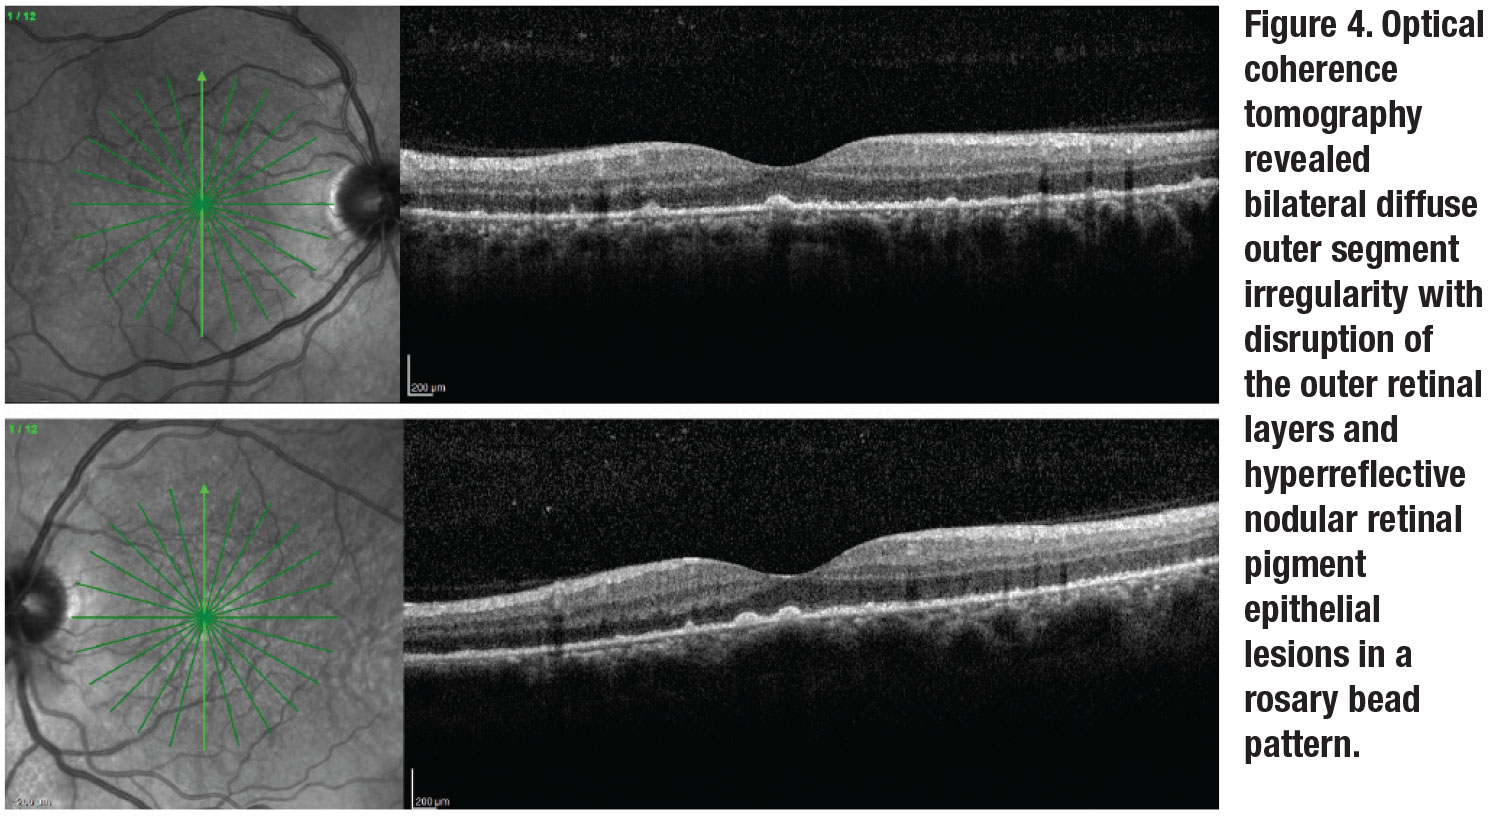

Fluorescein angiogram revealed bilateral hyperfluorescent staining of the placoid macular lesions and irregular hyperfluorescence nasally as well as some focal staining of the vessels and hyperfluorescence of the optic nerves (Figure 3). Optical coherence tomography revealed bilateral diffuse outer segment irregularity with widespread disruption of the outer retinal layers and hyperreflective nodular retinal pigment epithelium lesions (Figure 4).

The advent of OCT imaging has made it possible to report pathognomonic features of ASPPC, which include punctate hyperreflectivity in the choroid, disruption and loss of the ellipsoid zone, nodular irregularity of the retinal pigment epithelium and transient localized subretinal fluid.11,12